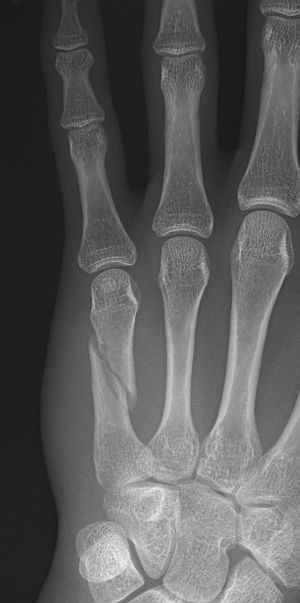

Bennett-fraktur = Green I: intraartikulär luxationsfraktur genom basen av metakarpale 1, volart-ulnart fragment ligger på plats medan APL-senan drar distala fragmentet radialt-proxmalt.

Rolando-fraktur = Green II: intraartikulär komminut fraktur genom basen av metakarpale 1, ofta Y- eller T-formad.

Tenneb-fraktur = omvänd bennettfraktur: intraartikulär fraktur i basen av metakarpale 5, volart-radialt fragment ligger på plats medan ECU-senan (extensor carpi ulnaris) drar distala fragmentet ulnart-proximalt.